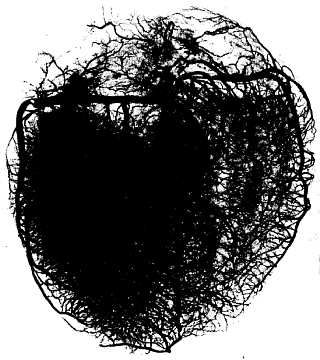

Рис. 210.Задняя поверхность сердца. Кровеносные сосуды.

1 - a. subclavia sinistra; 2 - a. carotis communis sinistra; 3 - truncus brachiocephalicus; 4 - v. azygos; 5 - v. cava superior; 6 - a. pulmonalis dextra; 7 - vv. pulmonales dextrae; 8 - atrium dextrum; 9 - v. cava inferior; 10 - v. cordis parva; 11 - a. coronaria dextra; 12 - r. interventricularis posterior; 13 - v. cordis media; 14 - ventriculus sinister; 15 - sinus coronarius; 16 - v. cordis magna; 17 - vv. pulmonales sinistrae; 18 - a. pulmonalis sinistra; 19 - lig. arteriosum; 20 - arcus aortae.